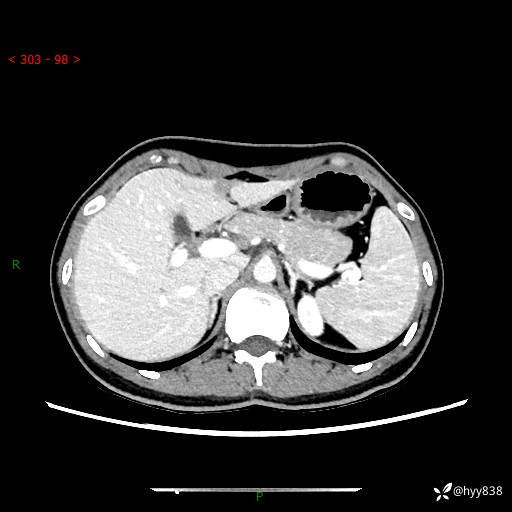

性别:女

年龄:23岁

简要病史:外院发现肝结节,来我院进一步增强确诊

上腹部CT平扫+增强

肝囊肿 (68)